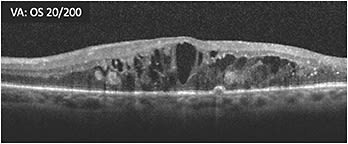

A 65-year-old male patient with proliferative diabetic retinopathy (PDR) who had undergone vitrectomy for nonclearing vitreous hemorrhage presented 2 months later. OCT showed substantial cystoid macular edema and hyperreflective foci (A) and he had poor vision (20/200 OS). The patient was started on treatment. Three months later, the retina was less swollen, but some macular edema remained, vision was 20/200, and cystic changes persisted (B). Treatment was switched within the same class in an effort to address the remaining macular edema. At 4 weeks following the initial treatment with the second therapy, vision remained poor (20/200 OS) and cystic spaces remained (C). Over the course of the next 8 months, the patient received 8 more treatments with the second therapy. Visual acuity was 20/100 -2 while the appearance of the cystic edema on OCT worsened (D).